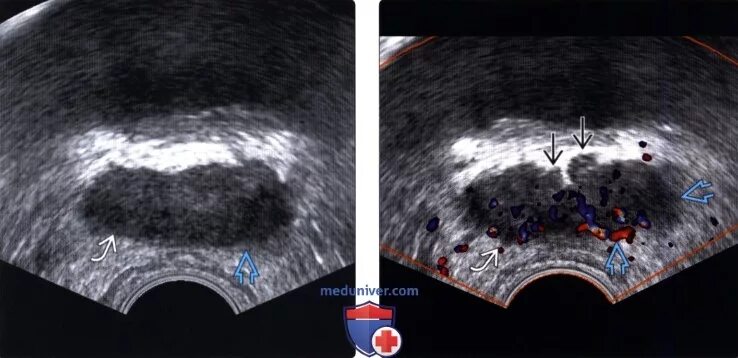

Простатит везикулит